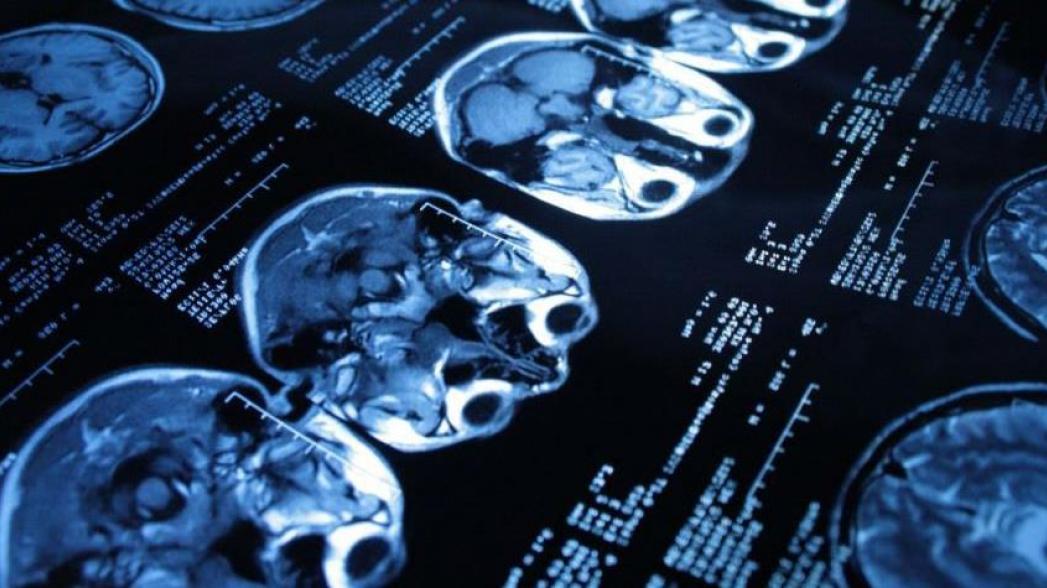

Искусственный интеллект для диагностики инсульта

Количество используемых в больницах изображений, полученных с помощью компьютерной томографии, увеличивается с каждым днем, а вот специалистов, которые могут действительно хорошо разбираться в таких сканах, недостаточно. Даже в таких развитых с точки зрения здравоохранения странах, как США. И здесь могут помочь системы на базе искусственного интеллекта.

Американская компания-стартап Realize.ai начала пилотный проект в Медицинском центре Северо-западного университета, в рамках которого их система, использующая алгоритмы искусственного интеллекта, применяется для идентификации разного рода отклонений в изображениях, полученных с помощью компьютерной томографии, пишет сетевое издание Built in Chicago. Эффективная расшифровка таких изображений может быть причиной для принятия решений, которые спасают жизнь человека. Ведь во многих случаях сканы позволяют выделить смертельно опасные симптомы, которые требуют немедленного внимания врачей

Разработчики надеются с помощью своей системы существенно ускорить процесс расшифровки таких изображений. Во-первых, система будет пытаться идентифицировать наиболее срочные сканы, чтобы радиологи занялись ими в первую очередь. Технология искусственного интеллекта будет также работать для выявления проблематичных зон на скане, для того чтобы ускорить весь процесс. В недалеком будущем, подобные алгоритмы глубокого обучения будут даже использоваться, чтобы работать в качестве т.н. "второго мнения", сравнивая просматриваемое изображение с гигантской базой аналогичных сканов с целью обнаружения аномалий и помощи радиологу, которые может что-то пропустить.

На первом этапе разработчики решили сфокусироваться на использовании системы для идентификации внутримозговых кровоизлияний, с которыми связано 10% всех инсультов, и просматривании сканов грудной клетки.